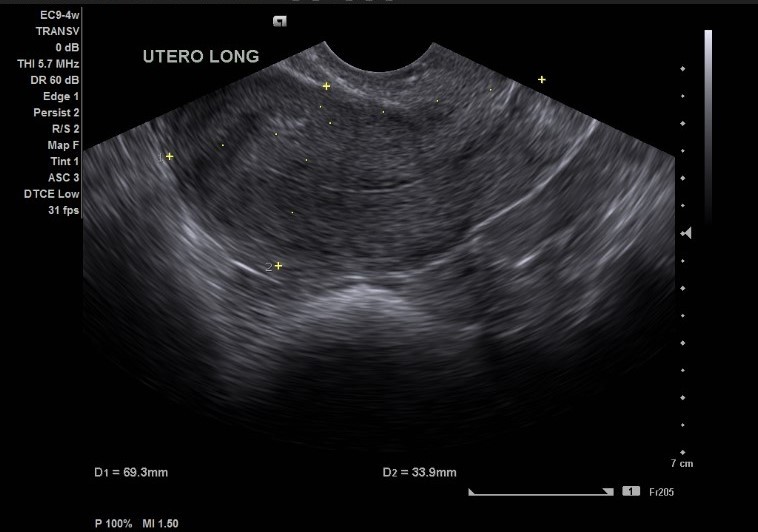

Ultrassom Morfológico Preço

Diagnósticos MédicosUltrassom morfológico preço acessível, você constata somente aqui, na SUA IMAGEM MEDICINA DIAGNÓSTICA, clínica empenhada em sempre melhor servir. Com profissionais dedicados e empenhados, nosso...

Ultrassom Morfológico

Ultrassom Morfológico

Ultrassom Morfológico

Diagnósticos MédicosOfertas incríveis um ultrassom morfológico você descobre somente aqui conosco, da SUA IMAGEM MEDICINA DIAGNÓSTICA, opção ideal para quem busca... Cotar Agora Saiba Mais

Ultrassom Morfológico Preço

Ultrassom Morfológico Preço

Ultrassom Morfológico Preço

Diagnósticos MédicosUltrassom morfológico preço acessível, você constata somente aqui, na SUA IMAGEM MEDICINA DIAGNÓSTICA, clínica empenhada em sempre melhor servir.... Cotar Agora Saiba Mais

Ultrassom Morfológica Preço

Ultrassom Morfológica Preço

Ultrassom Morfológica Preço

Diagnósticos MédicosAgilidade em ultrassom morfológica preço acessível, apenas a experiente e dedicada equipe da clínica SUA IMAGEM MEDICINA DIAGNÓSTICA poderá... Cotar Agora Saiba Mais